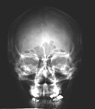

The radiograph of the human skull (shown at left) was taken using the conventional method discovered over 100 years ago. X-rays, created in the x-ray tube, pass through the body part and strike a photographic film. The film is loaded in a cassette, between two fluorescent screens. The screens glow when x-rays strike them, and expose the film in the same manner as all photographic film is exposed.